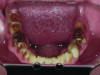

Pretreatment occlusal view of mandibular arch.

Figure 9

Functional: Attrition was noted on the teeth that were not protected with full-coverage crowns (Figure 8 and Figure 9). While wearing a Kois deprogrammer for about 1 month prior to restorative treatment, the mandibular teeth wore a notch in the deprogrammer platform, confirming clenching and the possibility of an impaired cortical control of the central pattern generator (Figure 10).1 All platform variables were verified and proper design of the Kois deprogrammer was followed. (The notch in the deprogrammer was repaired, leaving a smooth, flat surface to allow the proper position of the mandible to be determined.) The temporomandibular joint examination revealed normal opening with no joint sounds. The load and immobilization tests were normal. All the muscles, except the masseter, had no tenderness to palpation. Trigger points were palpable within the masseter muscles, which were hypertrophied. The diagnosis was determined to be occlusal dysfunction with the addition of awake bruxism and clenching. Upon questioning, the patient shared that he clenched while playing tennis daily, which he was very passionate about. The evidence that he was not grinding at night was the fact that tooth No. 11 was extremely cupped and not flattened. This ruled out a diagnosis of sleep bruxism, as the incisal edge would have become flat due to lateral movements of the mandible.

Biomechanical: Significant tooth structure loss had occurred between 2009 and 2017 (Figure 1 through Figure 3). Severe attrition had occurred on the anterior teeth, especially tooth No. 11. Severe erosion and abrasion were present on teeth Nos. 11, 18, 20, 21, 28, 29, 31, and 32 (Fig-

ure 4). The patient had generalized sensitivity, and tooth No. 18 was painful due to deep erosion, which approached the pulp chamber. Teeth Nos. 7 and 10 had moved out of position and rotated (Figure 5). The progression of erosion over the 8-year period could also be seen radiographically and was especially noticeable on tooth